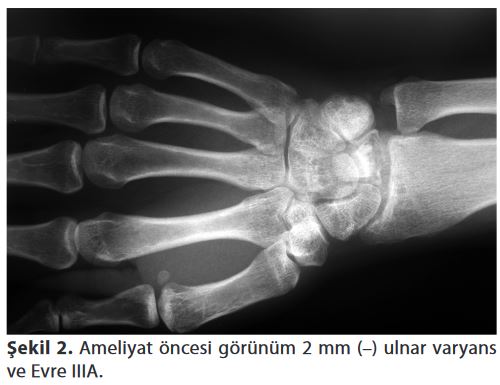

En sık Lichtman'ın radyolojik bulgulara göre tanımlamış olduğu sınıflandırma kullanılmaktadır (Tablo 1). Birinci evrede direkt grafiler normaldir, fakat MRG'de difüz sinyal intensite değişiklikleri vardır. İkinci evrede direkt grafilerde lunatumda difüz skleroz vardır. Üçüncü evre ikiye ayrılır: Evre IIlA'da lunatumda çökme vardır (genellikle hastalığın ilk tanımlandığı dönemdir). Evre IIIB'de lunatumdaki çökmeye kapitatumun proksimale yer değiştirmesi ve sakafolunat açının 60°'nin üzerine çıkması ile karpal yükseklik azalması eşlik eder. Evre IV'de lunatumdaki çökmeye radiokarpal ve midkarpal artroz eşlik eder (Tablo 1).

Mekanik olarak lunatumun üzerindeki yükün azaltılması, çökme ve hastalığın ilerlemesinin engellenmesi amacıyla eklem yüzeylerini dengeleyici yöntemler tercih edilir. Eklem yüzeylerinin dengelenmesi için nötral ya da +1 mm ulnar varyans oluşturulmaya çalışılır. Negatif ulnar varyansın düzeltilmesi işlemi ulnanın uzatılması ya da radiusun kısaltılması yoluyla yapılır (Şekil 2, 3). Eklem yüzeylerinin dengelenmesi için en sık uygulanan yöntem radial kısaltmadır, evre II, IIIA ve IIIB'de kullanılabilir. Bu tekniğin avantajları eklem dışı, uygulanması kolay ve etkili bir yöntem olmasıdır.